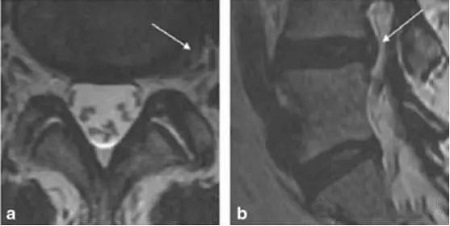

MRI示血小板注射前L4-5間盤膨出,箭頭示高密度區(qū)